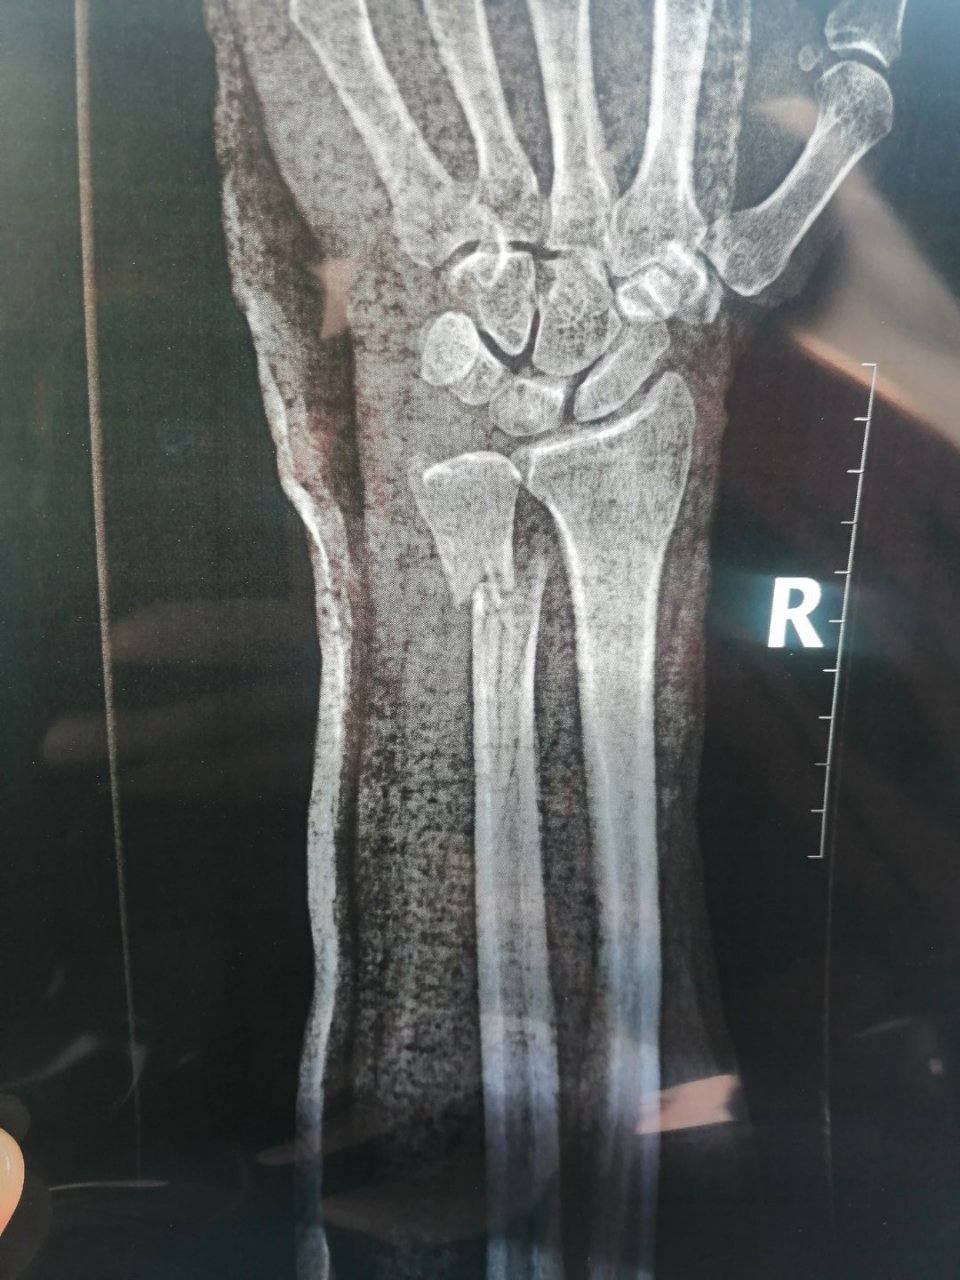

手腕ct图片高清,手腕正常ct图片

成都风湿医院患者治疗前腕关节ct检查.jpg

女,57岁,右手腕疼痛来诊.

请帮忙看下左腕舟骨骨折谢谢

神经受损没断,缺了一块,手腕骨折断裂,能评几级伤残

右手腕ct图片高清